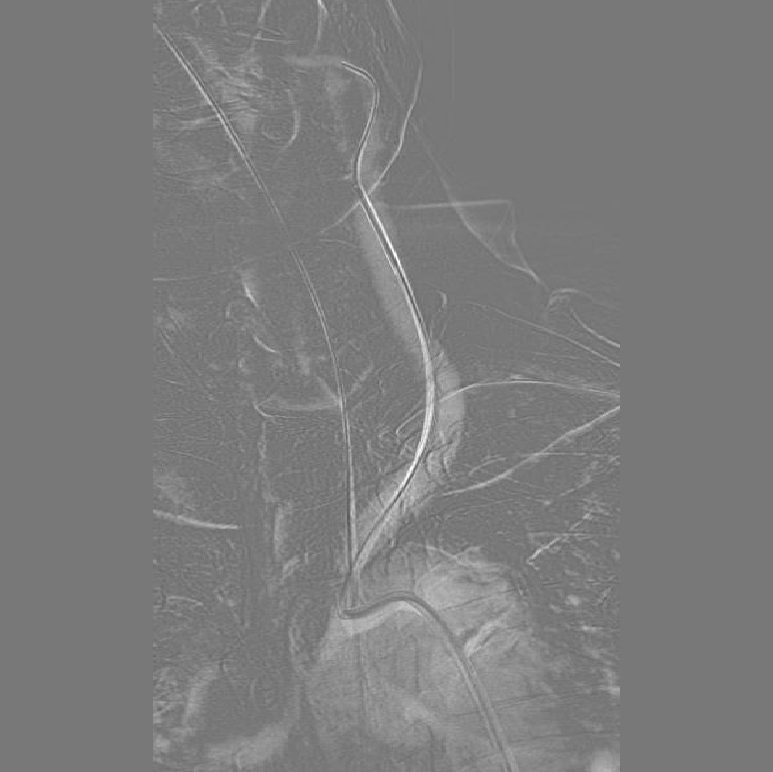

4、将微导丝+微导管小心通过狭窄部位,至于LMCA M1段,手推造影剂示真腔,撤出微导丝,送入长交换导丝撤出微导管,沿微导管送入赛诺2.0×10mm-152.8cm球囊至狭窄处,7atm充盈球囊及回抽,造影见狭窄较前改善,残余狭窄10%,远端血流速度改善,观察10分钟后造影见远端血流无明显变化。